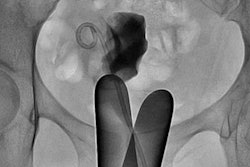

In cases of suspected deep endometriosis, European Society of Human Reproduction and Embryology guidelines recommend transvaginal ultrasound plus additional imaging to assess involvement in the ureter, bladder, bowel, and abdominal organs, the authors wrote. This additional imaging tends to be intravenous urography to evaluate the ureter and a double-contrast barium enema to evaluate the rectum, sigmoid, and cecum.

But IVU exposes women to radiation and DCBE requires the administration of contrast. That's why MRI is an intriguing option for preoperative assessment of endometriosis, the group noted.

Bielen and colleagues' study included 74 patients with clinically suspected endometriosis with urological and intestinal involvement who were referred for surgery between 2014 and 2015. All of the women underwent transvaginal ultrasound, DCBE, IVU, and abdominal MRI; gynecologists performed the ultrasound exams, while radiologists performed the DCBE, IVU, and MRI exams.

The combination of transvaginal ultrasound and MRI was correct in 86.5% of patients for assessing involvement of the bowel wall, gynecological structures, bladder, and ureters, the researchers found. The combination of transvaginal ultrasound, IVU, and DCBE was correct in 67.6% of patients (p = 0.02).